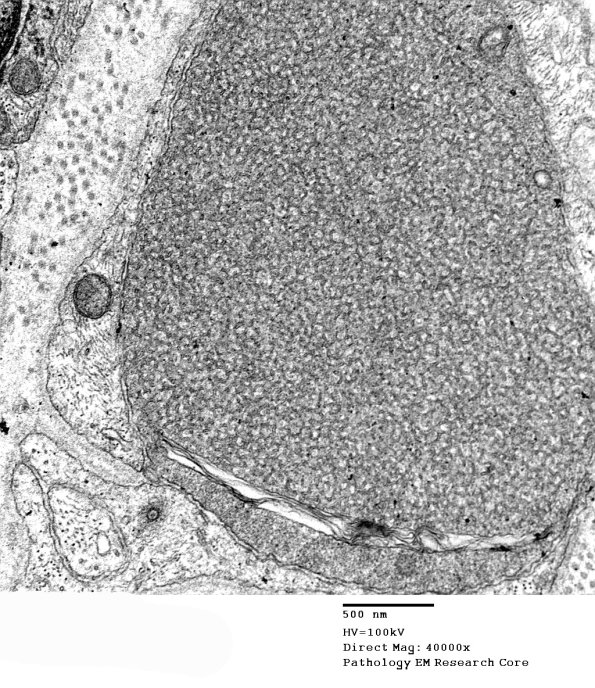

Higher magnification of image #1B1A. (electron micrograph)

1B1B Vitamin E Deficiency (Case 1) EM 041 - Copy